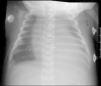

Caso 1Escolar de 4 años de edad que ingresa en la UCIP por dificultad respiratoria progresiva, precisando ventilación mecánica; como complicación presenta neumotórax bilateral por lo que se procede a inserción de tubo pleural (Pneumocath® 8F) en ambos hemitórax. Durante la inserción del tubo pleural derecho se produce fractura accidental del mismo, quedando un fragmento del mismo en la cavidad pleural (fig. 1). Se procede a su retirada mediante toracoscopia a los 6 días, sin incidencias.